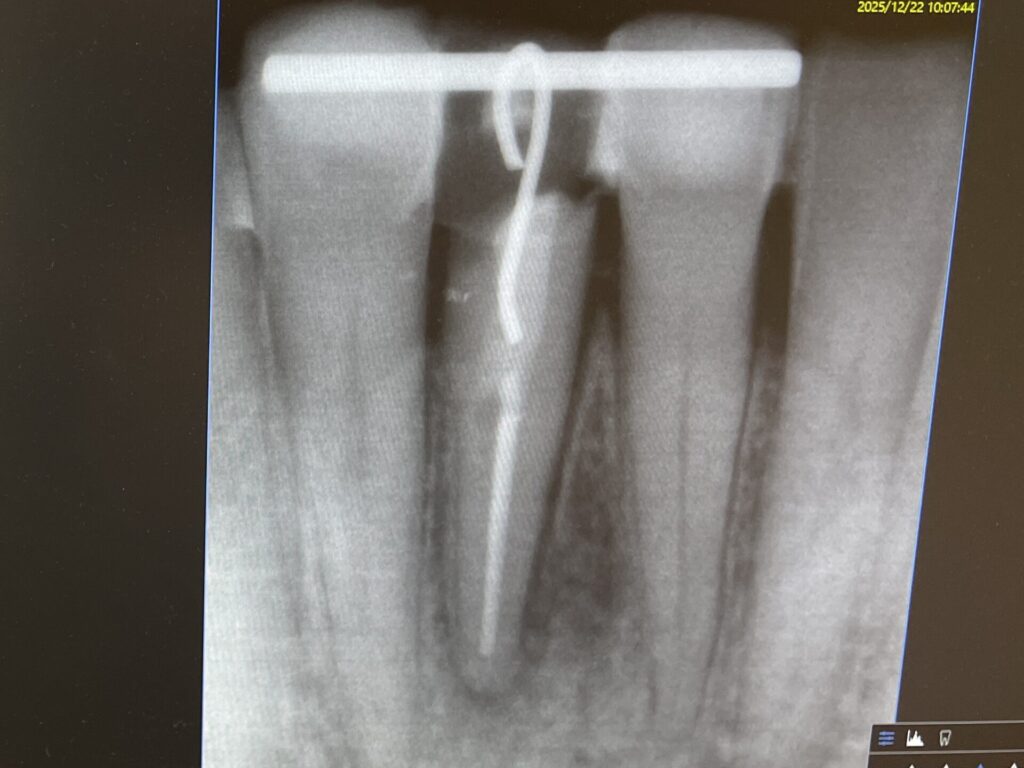

こちらが初診時のレントゲン写真です。歯が水平的に破折していて歯の一部が骨のトップに差し掛かっていることがわかります。

写真の青字:骨のライン

写真ピンク字:歯の断端